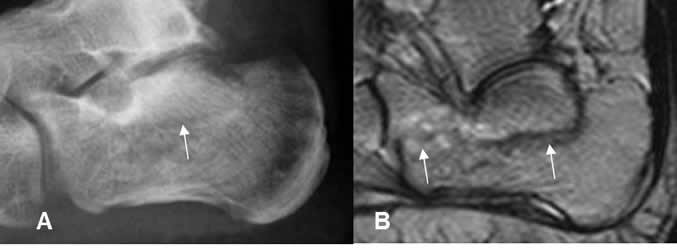

Fig 37. Fractura oblicua-transversa.

A: Rx tobillo AP y B: RM corte coronal. Fractura no desplazada del maléolo externo (Flecha delgada), con edema de tejidos blandos. (Flecha gruesa).